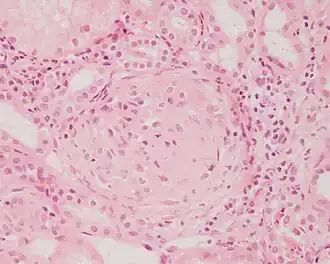

Микропрепарат биоптата из почки больного с гломерулонефритом